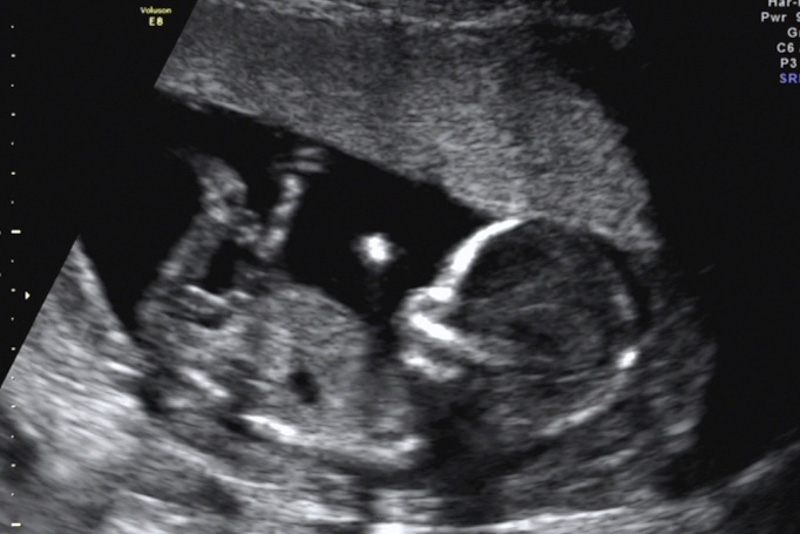

今年1月,石女士驚喜地發(fā)現(xiàn)自己懷孕了,然而在之后的孕檢過(guò)程中,檢查發(fā)現(xiàn)右附件區(qū)有一大小125mm×115mm×79mm囊性占位,混合回聲,考慮右側(cè)卵巢成熟畸胎瘤。由于囊腫巨大,內(nèi)部回聲雜亂,隨著孕期的增加,囊腫有可能發(fā)生扭轉(zhuǎn),導(dǎo)致破裂引起急性腹痛威脅母嬰安全。同時(shí),巨大的腹腔占位可能影響子宮增大,限制胎兒的生長(zhǎng)……

因患者腫塊巨大,孕期手術(shù)風(fēng)險(xiǎn)高,醫(yī)院立即組織了婦科、產(chǎn)科、放射科、超聲醫(yī)學(xué)科、麻醉科、藥學(xué)部等開(kāi)展了MDT會(huì)診。患者囊性占位中有大小約7cm的實(shí)性占位,手術(shù)需要考慮盡量減少手術(shù)后腹腔黏連,同時(shí)需要將占位完整切除,盡量減少對(duì)腹腔和子宮的干擾,才能最大程度保證孕期平穩(wěn)和母嬰安全,經(jīng)過(guò)全面考慮和深入討論,專家團(tuán)隊(duì)為患者制定了詳細(xì)的治療方案,決定行經(jīng)臍單孔腹腔鏡下行卵巢囊腫剔除手術(shù)。

在大家的共同努力下,患者長(zhǎng)在卵巢上的腫瘤被完整剝除,腹腔干凈,對(duì)子宮沒(méi)有騷擾,卵巢恢復(fù)正常大小,臍部術(shù)口自然成形,不留瘢痕,監(jiān)測(cè)胎心正常,手術(shù)順利結(jié)束!